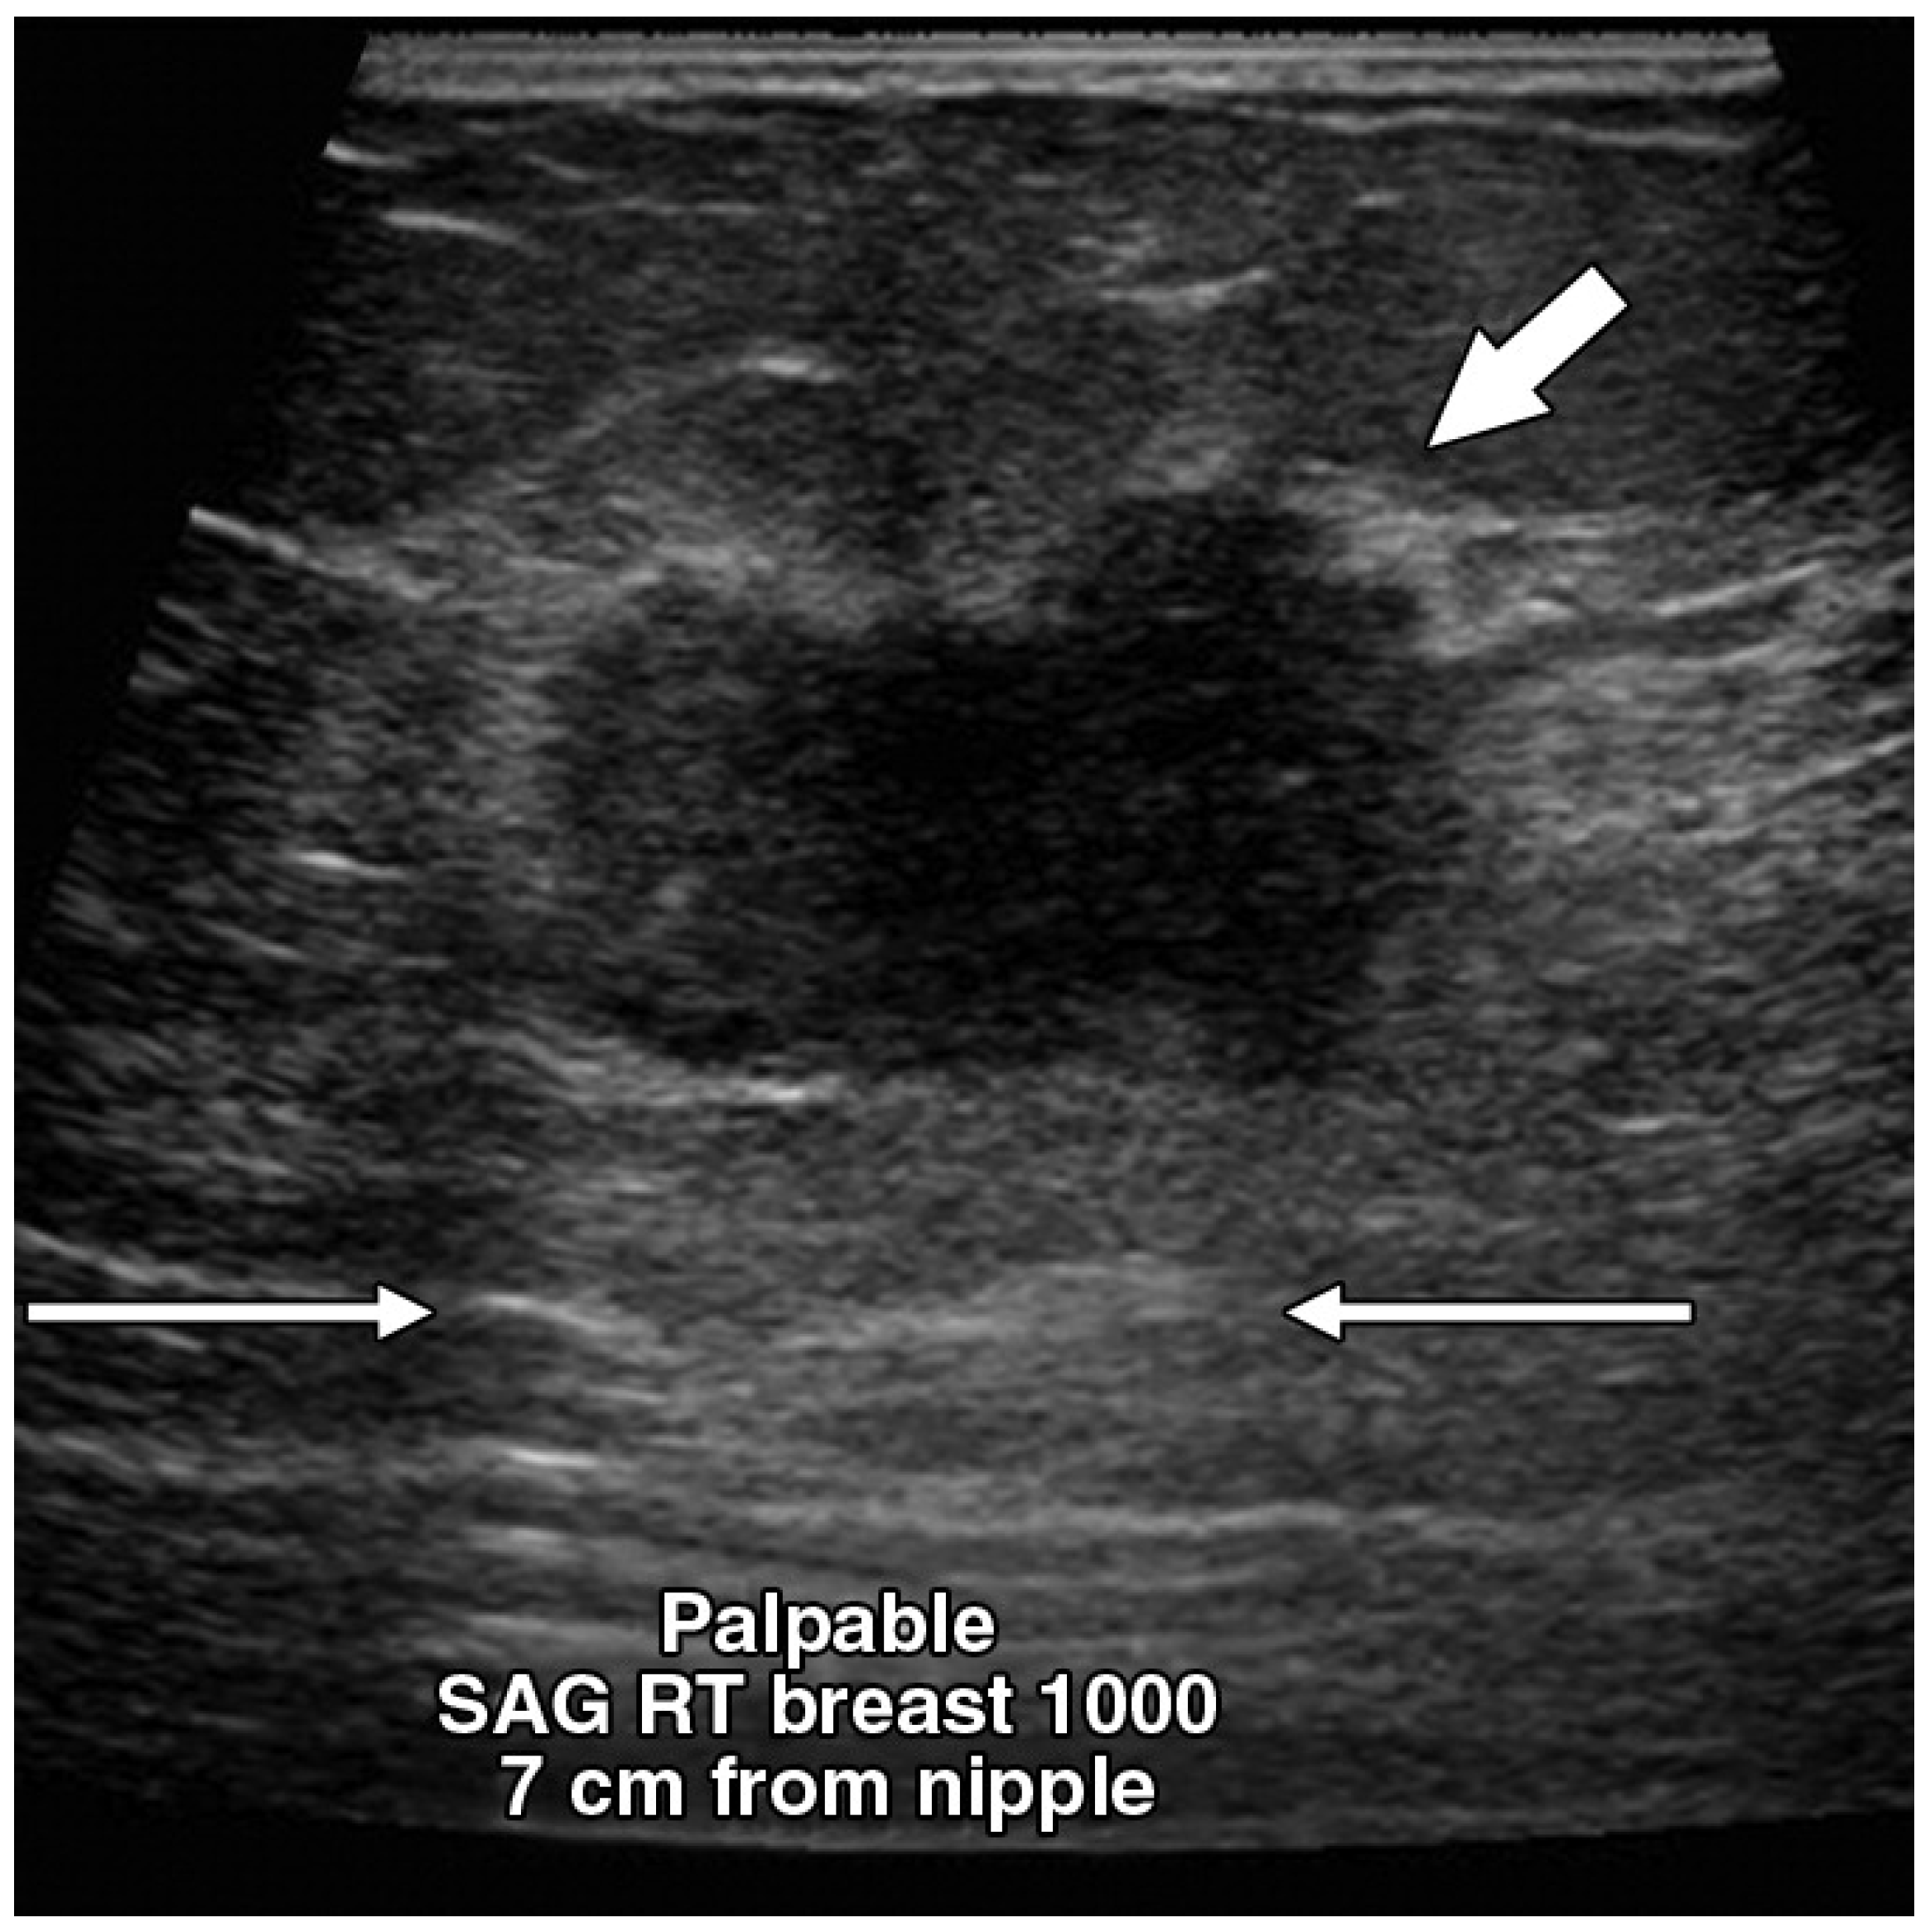

2.2. Ultrasound

- Kim, S.H.; Bo Kyoung Seo, J.L.; Kim, S.J.; Cho, K.R.; Lee, K.Y.; Je, B.K.; Kim, H.Y.; Kim, Y.S.; Lee, J.H. Correlation of ultrasound findings with histology, tumor grade, and biological markers in breast cancer. Acta Oncol. 2008, 47, 1531–1538. [Google Scholar] [CrossRef]

- Lamb, P.M.; Perry, N.M.; Vinnicombe, S.J.; Wells, C.A. Correlation Between Ultrasound Characteristics, Mammographic Findings and Histological Grade in Patients with Invasive Ductal Carcinoma of the Breast. Clin. Radiol. 2000, 55, 40–44. [Google Scholar] [CrossRef]

- Bae, M.S.; Han, W.; Koo, H.R.; Cho, N.; Chang, J.M.; Yi, A.; Park, I.A.; Noh, D.Y.; Choi, W.S.; Moon, W.K. Characteristics of breast cancers detected by ultrasound screening in women with negative mammograms. Cancer Sci. 2011, 102, 1862–1867. [Google Scholar] [CrossRef]

- Irshad, A.; Leddy, R.; Pisano, E.; Baker, N.; Lewis, M.; Ackerman, S.; Campbell, A. Assessing the Role of Ultrasound in Predicting the Biological Behavior of Breast Cancer. Am. J. Roentgenol. 2013, 200, 284–290. [Google Scholar] [CrossRef]

- Gokhale, S. Ultrasound characterization of breast masses. Indian J. Radiol. Imaging 2009, 19, 242–247. [Google Scholar] [CrossRef]